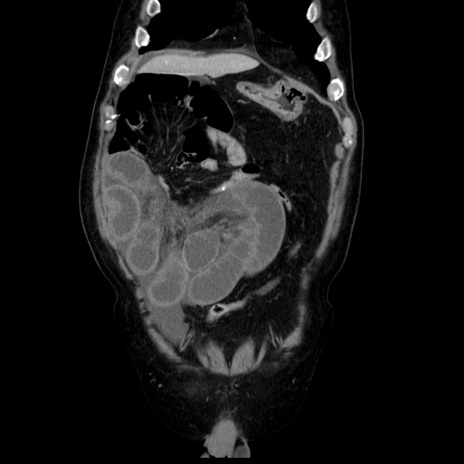

症例30(冠状断像)

【症例】80歳代男性

【主訴】臍周囲痛

【現病歴】約6時間前から臍下部痛が出現。次第に腹部膨隆・背部痛も生じてきたため来院。背部痛の場所は変化しない。

【身体所見】意識清明、BT 36.3℃、BP  131/87mmHg、P 87bpm、SpO2 100%(RA)、臍周囲自発痛・圧痛あり、反跳痛なし、自発痛部位に一致して板状硬あり、腹部膨隆、腸雑音減弱、CVA tenderness両側陰性。

【データ】WBC 19600、CRP 0.33